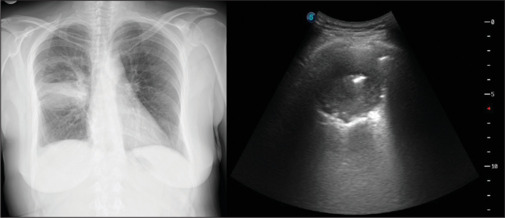

胸部超声(TUS)是一种长期建立的成像方式,在诊断许多胸膜实质疾病方面具有公认的有效性和可靠性。肺脓肿(LA)是一种以肺实质内液化性坏死和空化为特征的传染病,多见于免疫抑制患者或有多种危险因素的患者。它的治疗包括有效的抗生素治疗,在极少数情况下,引流或手术。在可行的情况下,从LA获取样本对于根据培养物中鉴定的病原体启动靶向治疗至关重要。在这个病例报告中,我们提出了一个44岁的女性患者住院的洛杉矶。脓肿通过超声显像,在超声引导下取样,并在持续的超声监测下成功处理。

Thoracic ultrasonography (TUS) is a long-established imaging modality with proven efficacy and reliability in the diagnosis of numerous pleuro-parenchymal diseases. Lung abscess (LA) is an infectious disease characterized by liquefactive necrosis and cavitation within the pulmonary parenchyma, typically occurring in immunosuppressed patients or those with various risk factors. Its treatment involves effective antibiotic therapy and, in rare cases, drainage or surgery. Obtaining a sample from the LA, when feasible, is crucial for initiating targeted therapy based on the pathogen identified in the culture. In this case report, we present a 44-year-old female patient hospitalized for an LA. The abscess was visualized via TUS, sampled under ultrasound guidance and successfully managed with ongoing ultrasonographic monitoring.